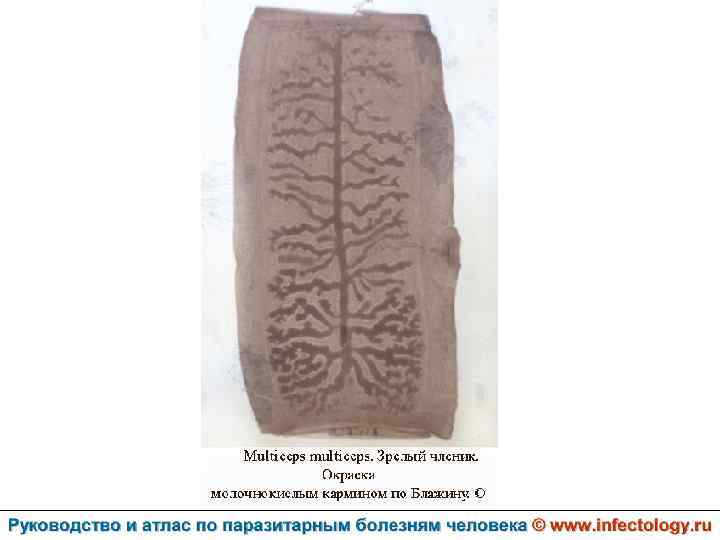

Ценуроз (шифр по МКБ 10 – B 71. 8)– спорадически встречающееся заболевание человека, вызываемое личиночной формой (ценуром) гельминтов рода Multiceps, половозрелые формы которых паразитируют у собак и диких волчьих. . Проявляется разнообразными клиническими симптомами в зависимости от вида паразита.